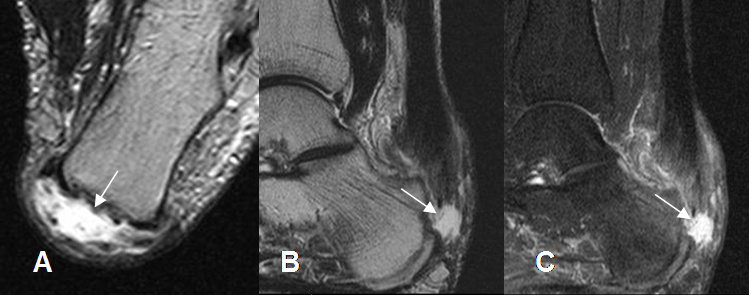

Fig 86. Ruptura insercional del aquiles.

A: RM axial en T2. Area hiperintensa sobre la inserción del aquiles, por ruptura.

B: RM sagital en T2 y C: RM sagital en STIR. Solución de continuidad del tendón a nivel de su inserción, con cambios inflamatorios agudos en los tejidos vecinos.